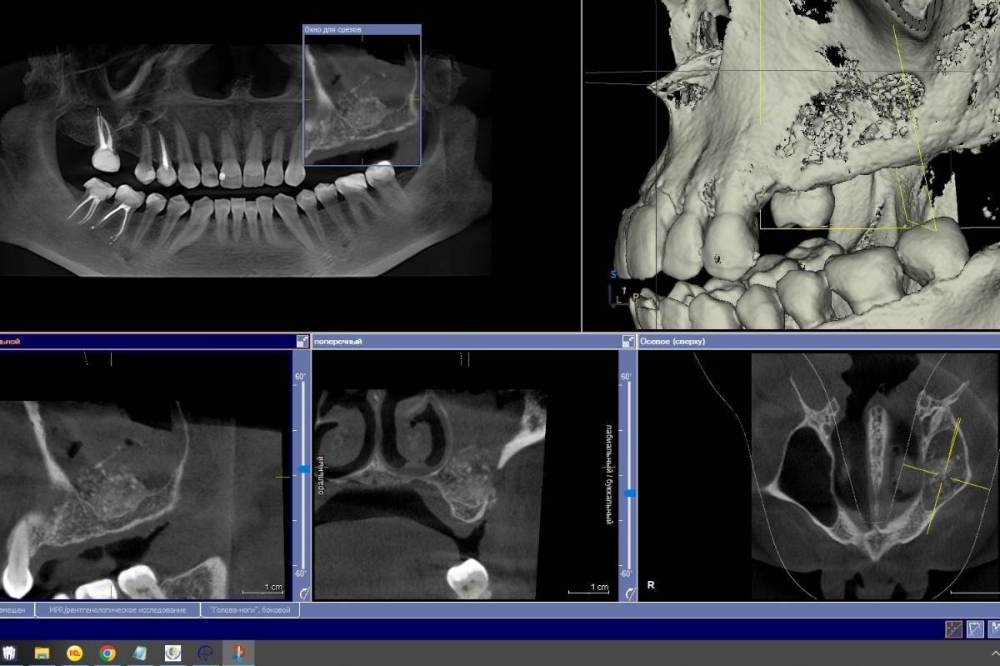

Ponchik Опубликовано 27 ноября, 2022 Поделиться Опубликовано 27 ноября, 2022 Неделю назад проведён синуслифтинг. Через 4-5 дней заболело горло. Вчера начался "НАСМОРК" Сегодня осмотр. Сделал КТ. Обработал местно антисептиками. Назначил Цефотаксим, Полидексу, Аквамарис (до этого был амоксиклав) отпустил до четверга. Вопрос: может зря я решил наблюдать? Надо было раскрыть и всё убрать? Просто растерялся. Первый раз за 6лет (как начал делать) синус проинфицировался. Ссылка на комментарий

Irouil Опубликовано 27 ноября, 2022 Поделиться Опубликовано 27 ноября, 2022 Готовиться нужно к худшему, выглядит с большой долей вероятности на выход. Но я бы согласился с Антоном, консервативную терапию никто не отменял. Гипертон нужно в аэрозоле, а не в обычном спрее, желательно перед гипертоном гормон, а после него топический а/б и виброцил до кучи, 2 раза в день, в обе ноздри, недели 3 (кроме а/б). Что Вы теряете? Через месяц после операции я бы повторил КТ, если бы увидел такой же разброс графта в основном конгломерате + симптоматика, конечно - удалять все. Ссылка на комментарий

Irouil Опубликовано 27 ноября, 2022 Поделиться Опубликовано 27 ноября, 2022 @TIGER судя по тому, что просвет пазухи не полностью затенен и что есть в анамнезе насморк, что-то из неё вытекает, иначе там было бы все однородно плохо. Сделать КТ ОНП не будет лишним, согласен. 1 Ссылка на комментарий

Ponchik Опубликовано 27 ноября, 2022 Автор Поделиться Опубликовано 27 ноября, 2022 3 часа назад, TIGER сказал: @Ponchik дренаж работает?(соустье) Да. Работает. Отделяемое из носа есть и по кт видно как вся эта куча графта, с» и жидкости тянется к соустью. Срез просто выбран по середине графта в зоне операции. Вопрос второй назрел. Кто виноват? Всё закисло на первой неделе. Лоскут лежит вроде нормально. Можно считать инфицирование произошло во время операции? Грешить на обработку поля, рук и инструментов? Или? Пациент очень боялся именно такого исхода. Я выдал больничный и человек старался из дома нос не высовывать. Ссылка на комментарий